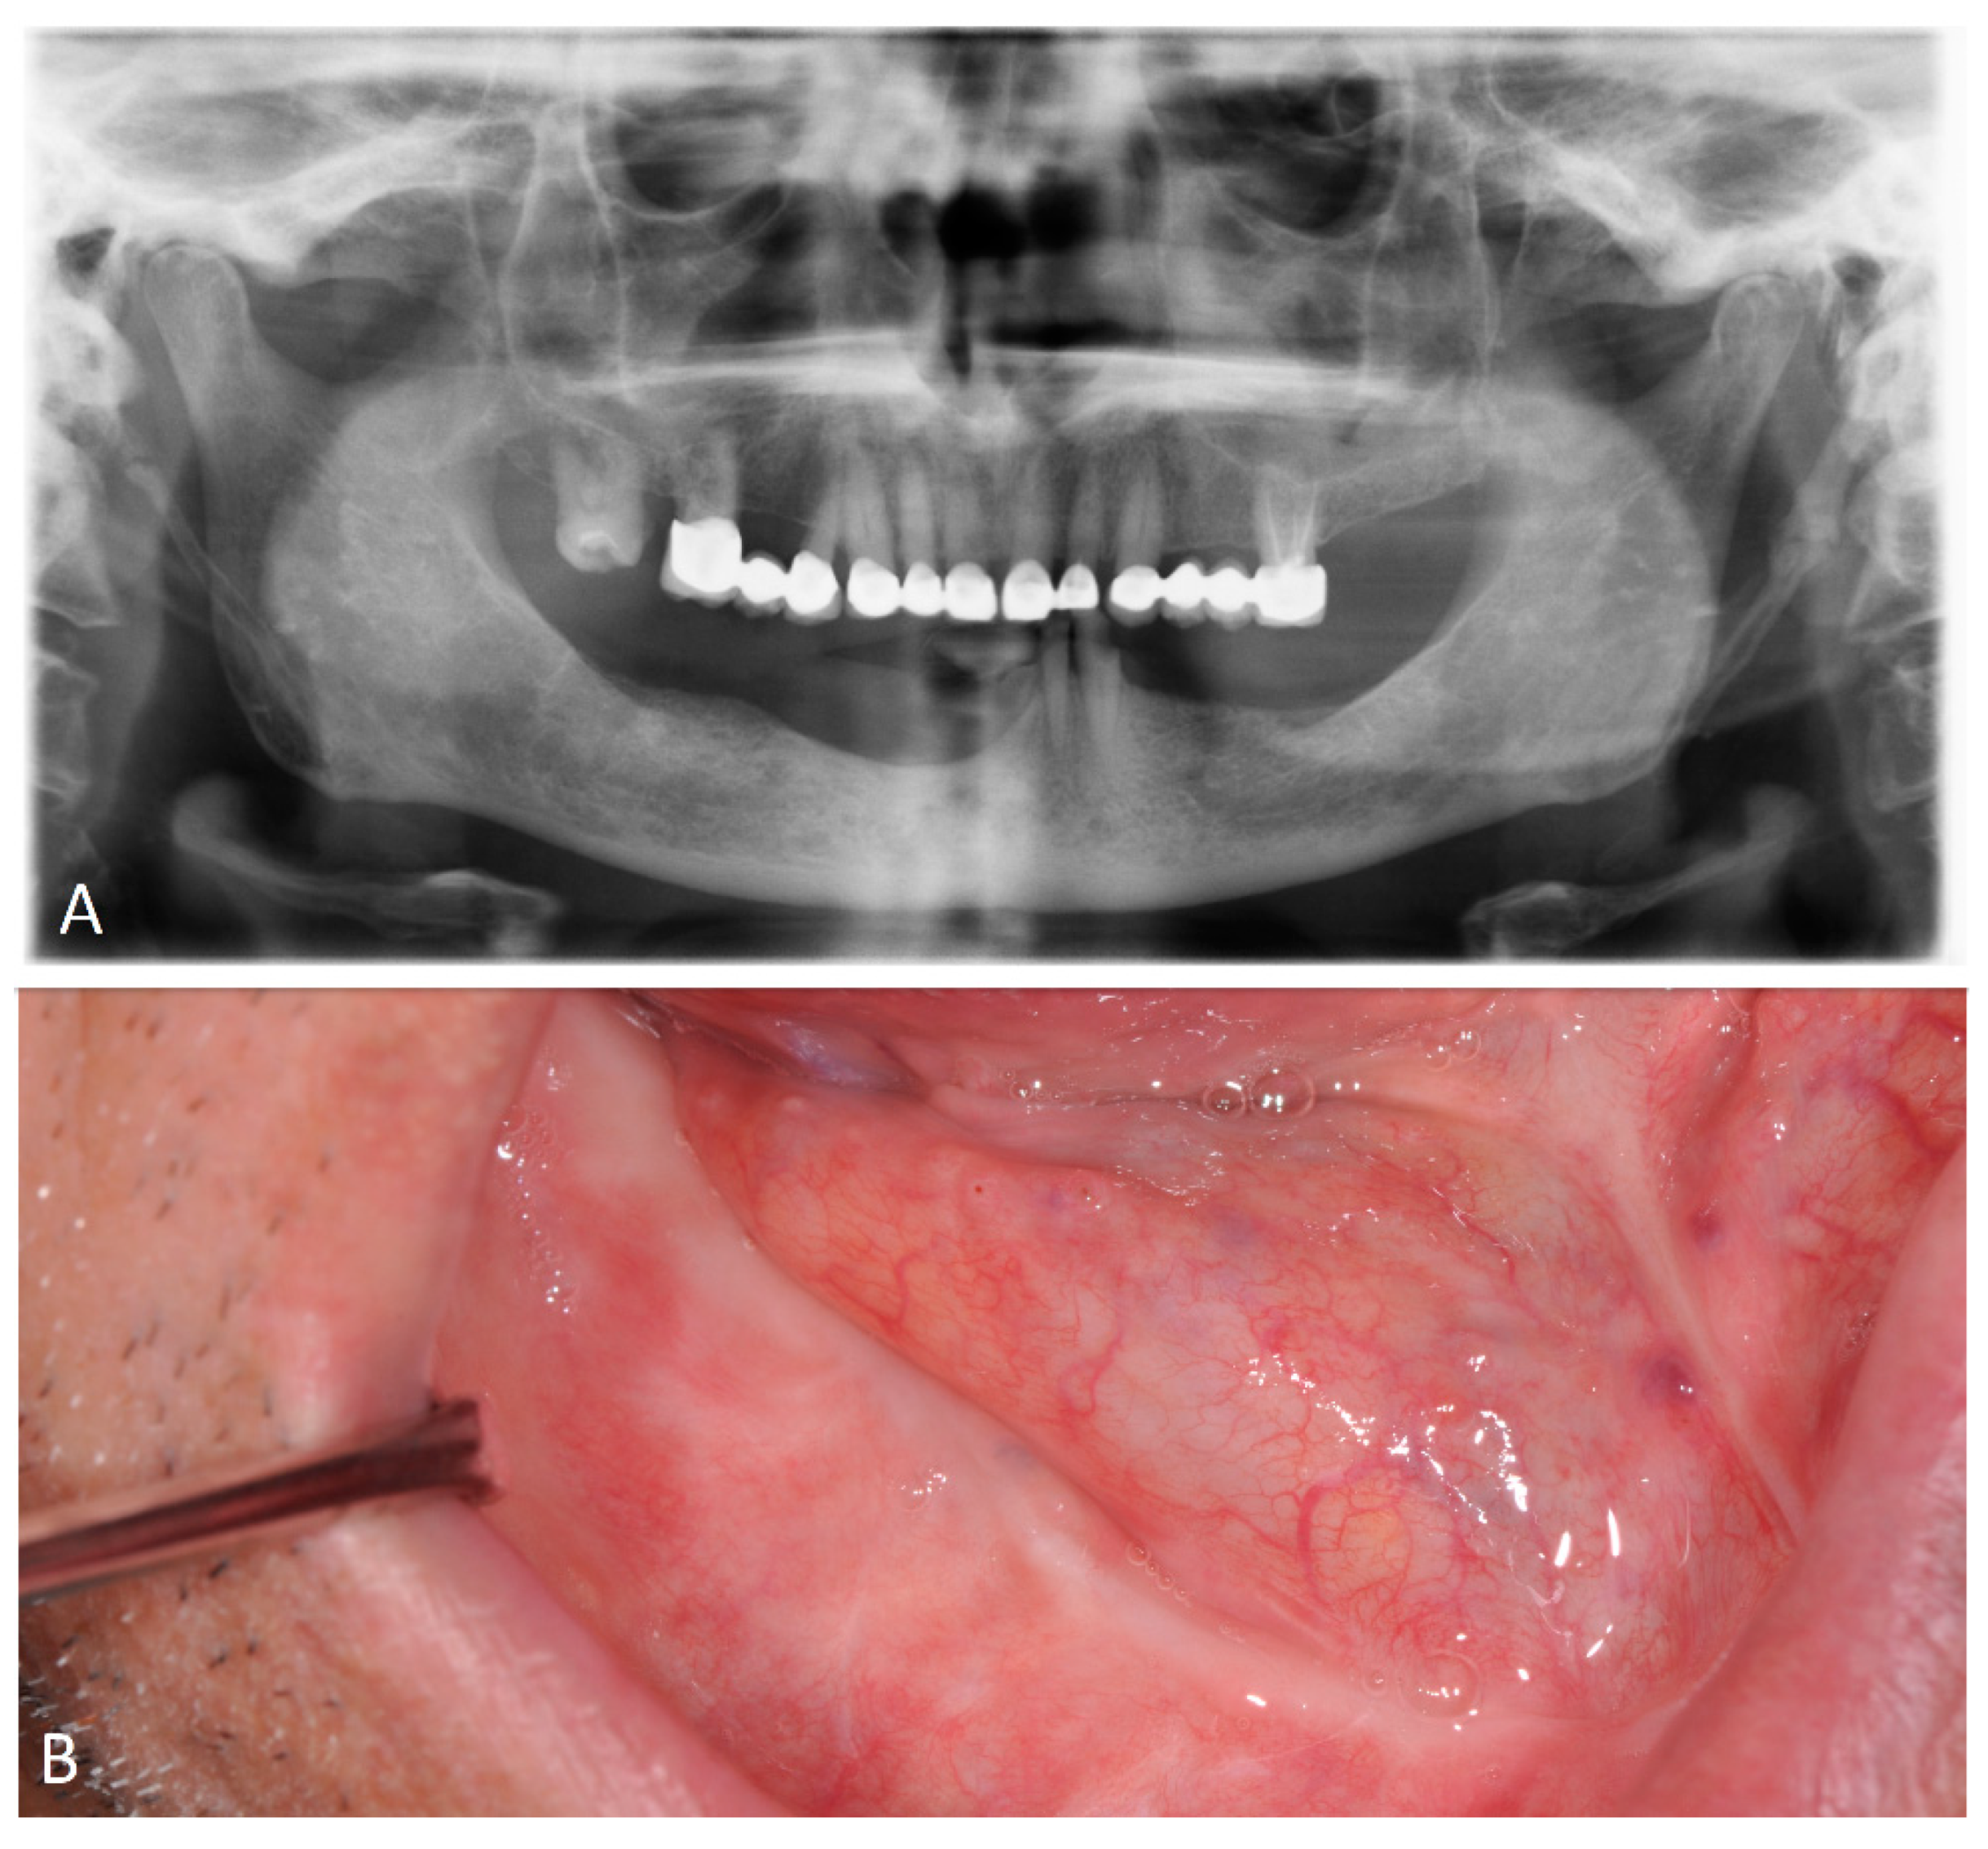

4.8. Case Presentation